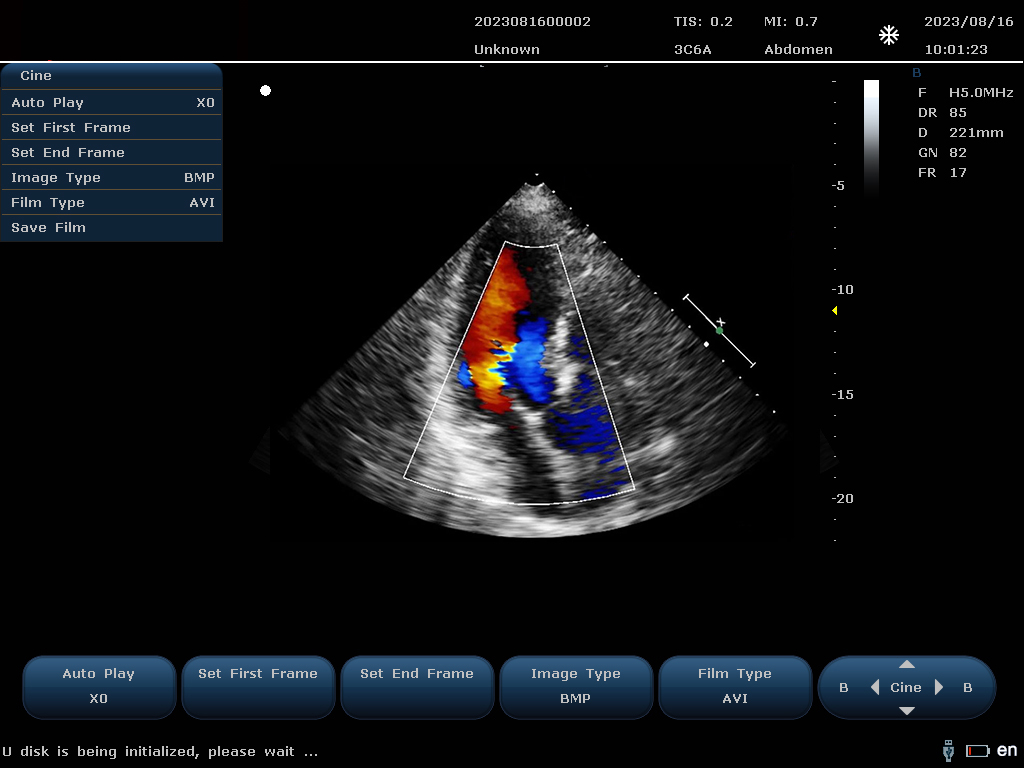

设备通过检测这些频移信号,并利用复杂的信号处理技术,包括傅立叶变换等,分析血流的方向、速度和分布。彩色编码后,血流信息被叠加在传统的黑白超声二维图像上,形成彩色多普勒图像,直观显示血流动态。

最终,这些信息转化为图像显示在屏幕上,医生可以根据图像中血流的颜色(通常红色代表血流朝向探头,蓝色代表远离探头)和亮度来判断血流的性质和异常情况,如血流速度增快可能指示狭窄,无血流区域可能意味着阻塞等。